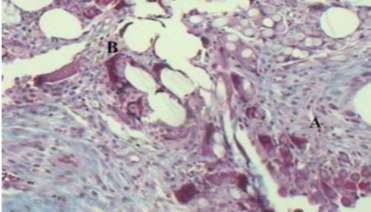

Hình 1.16. Phản ứng viêm tế bào hạt dị vật (A), tế bào sợi xơ (B), độ phóng đại 100 lần, sau đặt lưới polypropylene/polyglactin tìm thấy dưới kính hiển vi.

Hình 1.17. A. Phản ứng tế bào hạt dị vật tìm thấy kín đáo khi đặt lưới polypropylene, phản ứng viêm tối thiểu B. Tế bào sợi xơ giảm, phóng đại 100 lần. Nguồn: Goldenberg A. et al., (2005) [62].